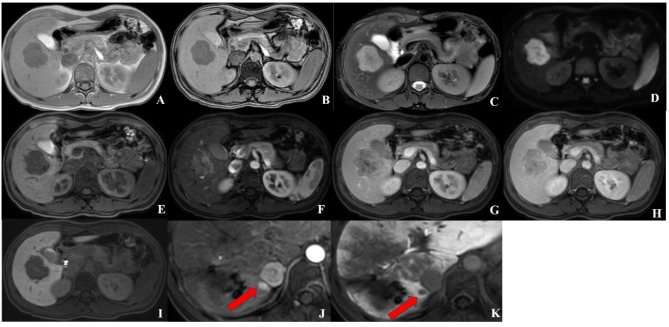

Methods: This retrospective study included 73 patients with MVI-negative HCC who underwent Gadoxetic acid-enhanced MRI (EOB-MRI) scanning before surgical resection. The clinical factors and LI-RADS v2018 MRI features associated with early recurrence were determined using univariable and multivariable analyses. A diagnostic model predicting early recurrence after surgical resection was developed, and its predictive ability was evaluated via a receiver operating characteristic curve. Then, the recurrence-free survival (RFS) rates were analyzed by Kaplan-Meier method.

Results: In total, 26 (35.6%) patients were diagnosed with early recurrence according to the follow-up results. Infiltrative appearance and targetoid hepatobiliary phase (HBP) appearance were independent predictors associated with early recurrence (p < 0.05). For the established diagnostic model that incorporated these two significant predictors, the AUC value was 0.76 (95% CI: 0.64-0.85) for predicting early recurrence after resection, which was higher than the infiltrative appearance (AUC: 0.67, 95% CI: 0.55-0.78, p = 0.019) and targetoid HBP appearance (AUC: 0.68, 95% CI:0.57-0.79, p = 0.028). In the RFS analysis, patients with infiltrative appearance and targetoid HBP appearance showed significantly lower RFS rates than those without infiltrative appearance (2-year RFS rate, 48.0% vs. 72.0%; p = 0.009) and targetoid HBP appearance (2-year RFS rate, 60.0% vs. 35.0%; p = 0.003).

Conclusion: An EOB-MRI model based on infiltrative appearance and targetoid HBP appearance showed good performance in predicting early recurrence of HCC after surgery, which may provide personalized guidance for clinical treatment decisions in patients with MVI-negative HCC.